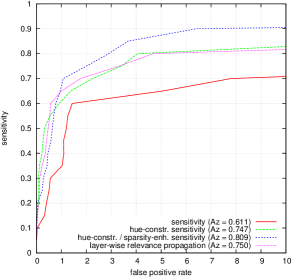

FROC curves are reported in Fig. 6 for ‘net B’; areas under the limited FROC curve for all three ConvNets are summarized in Table 3. It appears that the number of false alarms is rather large, particularly in the case of microaneurysm detection. The reason is that human experts primarily segmented the most obvious lesions, while screening algorithms need to focus on the most subtle lesions as well. In other words, many true lesions are counted as false alarms. Of course, this comment also applies to competing automatic solutions. To show the value of our detections, the proposed solution was compared in Fig. 7 to results reported in the literature, following the DiaretDB1 standardized procedure (see section 5.3.2). Most authors reported a single (sensitivity, specificity) pair: this is what we reported in Fig. 7. Some authors reported ROC curves; in that case, we also reported a single (sensitivity, specificity) pair: the one closest to the (sensitivity = 1, specificity = 1) coordinate. Note that all competing solutions (Kauppi et al., 2007; Yang et al., 2013; Franklin and Rajan, 2014; Kumar et al., 2014; Bharali et al., 2015; Mane et al., 2015; Dai et al., 2016) are trained at the lesion level, while ours is trained (in Kaggle-train) at the image level.

Three ConvNets were trained to detect referable DR in the Kaggle-train dataset, using the proposed heatmap optimization procedure. Then, we evaluated how well those ConvNets could detect lesions in the DiaretDB1 dataset, without retraining them. For lesion detection at the image level, they outperformed previous algorithms, which were explicitly trained to detect the target lesions, with pixel-level supervision (see Fig. 7). This superiority was observed for all lesions or groups of lesions, with the exception of ‘red lesions’. Experiments were also performed at the lesion level: for all lesion types, the proposed algorithm was found to outperform recent heatmap generation algorithms (see Table 3). As illustrated in two examples (see Fig. 9 and 10), the produced heatmaps are of very good quality. In particular, the false alarms detected on the vessels, in the vicinity of true lesions in the unoptimized heatmaps ( maps), are strongly reduced with sparsity maximization (, , ). These experiments validate the relevance of image-level supervision for lesion detectors, but stress the need to optimize the heatmaps, as proposed in this paper. Note that detection performance is not affected much by image quality: very good detections are produced in the blurry image obtained with a low-cost, handheld retinograph (see Fig. 10). This is a very important feature, which opens the way to automated mobile screening. However, it can be observed that the ‘AlexNet’ architecture, which achieves moderate DR detection results, also achieves poor detection results at the lesion level, even after heatmap optimization (see Table 3): to ensure good detection performance at the lesion level, the proposed optimization framework should be applied to ConvNet architectures that achieve good image-level performance.